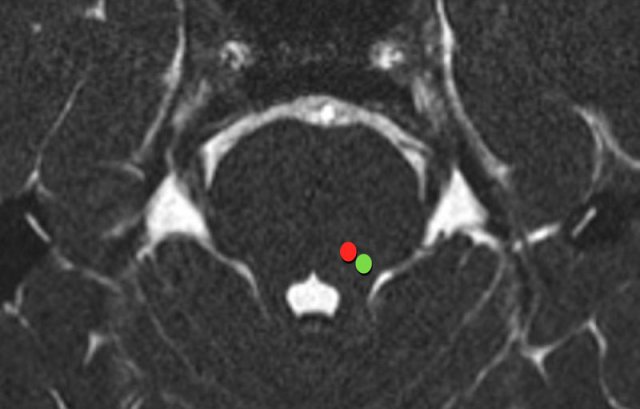

The trigeminal nerve originates from two separate nuclei in the pons: the sensory division from the sensory nucleus (green dot) and the motor division from the motor nucleus (red dot).

The sensory nucleus is situated laterally in the tegmentum, anterolateral to the fourth ventricle (green dot).

The motor nucleus is situated anteromedial to the sensory nucleus (red dot).